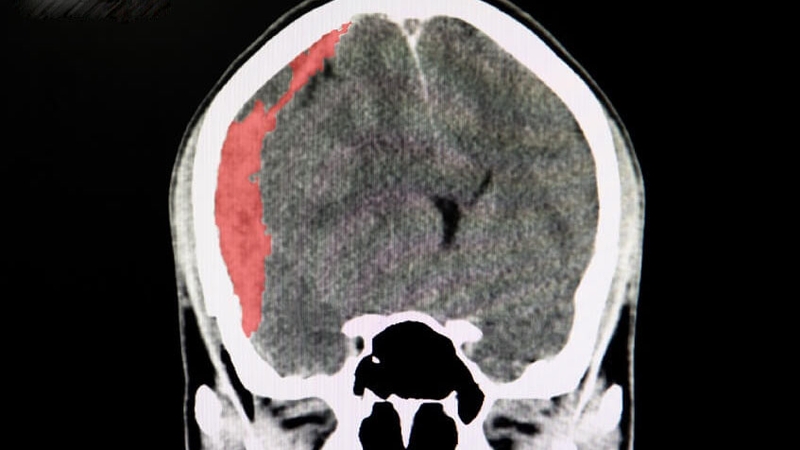

Chấn thương não, chẳng hạn như tụ máu não, thường đe dọa tính mạng và cần được chăm sóc y tế ngay lập tức. Khi gặp phải tình trạng này, hầu hết bệnh nhân và gia đình họ thường băn khoăn không biết một người bị tụ máu não sống được bao lâu và tiên lượng ra sao. Bài viết sau đây sẽ cung cấp thông tin chi tiết để giải đáp những thắc mắc này.

Tụ máu não xảy ra khi các mạch máu trong não bị vỡ do chấn thương, huyết áp cao hoặc các tình trạng bệnh lý khác, dẫn đến tình trạng máu ứ đọng ở các vùng cụ thể của não. Điều này có thể dẫn đến các biến chứng nghiêm trọng, bao gồm nguy cơ đột quỵ xuất huyết hoặc tử vong. Do đó, không ai được chủ quan khi bản thân hoặc người thân của mình gặp phải tình trạng tụ máu não.

Tụ máu não là tình trạng máu tích tụ trong não do các mạch máu bị vỡ. Tình trạng này có thể do nhiều yếu tố gây ra như chấn thương sọ não, vỡ phình động mạch hoặc dị dạng mạch máu não. Máu tích tụ tạo thành cục máu đông đè lên mô não, dẫn đến các biến chứng thần kinh. Tùy thuộc vào vị trí, tụ máu não được phân loại thành một số loại: